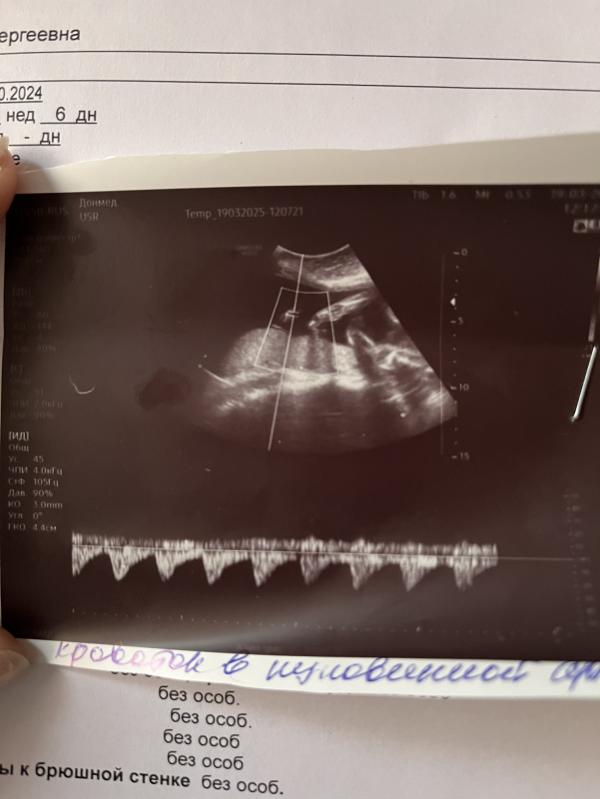

Малыш поднабрал массу,гипоксия практически ушла,кровоток улучшился!!!и Гинеколог,и гематолог ,и я с мужем,естественно,довольны результатами УЗИ!🫶но не останавливаемся и идем дальше!!!препараты и уколы практически до самых родов(да и фиг с ними😁)

Малыш Активен,уже не открывает рот от нехватки кислорода!

Как сказала гематолог-поборемся за кровоток в пуповине,а затем и за кровообращение в мозгу